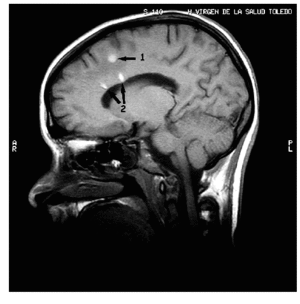

Mujer de 18 años de edad que ingresa con una puntuación en la escala de coma de Glasgow (CGS) de 5 por traumatismo craneoencefálico tras un accidente de tráfico. La tomografía computarizada (TC) realizada al ingreso mostró pequeñas contusiones hemorrágicas frontales y temporales izquierdas, pequeño sangrado interhemisférico anterior y ventricular izquierdo, hemorragia subaracnoidea en convexidad y edema difuso. Se iniciaron medidas estándar para el tratamiento de la hipertensión intracraneal hasta constatarse el control de la presión intracraneal y la disminución del tamaño de las contusiones y el edema cerebral. La evolución neurológica de la paciente no fue favorable, mantuvo una GCS de 9 puntos que no se justificó con los hallazgos radiológicos descritos hasta el momento. Se realizó una resonancia magnética craneal en la que se observaron una lesión intraparenquimatosa (indicada con 1 en la imagen), ya objetivada en la TC, y 2 lesiones hemorrágicas en el cuerpo del cuerpo calloso y perpendiculares a los ventrículos (indicada con 2 en la imagen), posiblemente por mecanismo de cizallamiento, compatibles con el diagnóstico de lesión axonal difusa. Después de 28 días de ingreso en la unidad de cuidados intensivos, la paciente presenta una GCS de 10 puntos, con apertura ocular espontánea, respuesta motora de localización al dolor y ausencia de respuesta verbal.